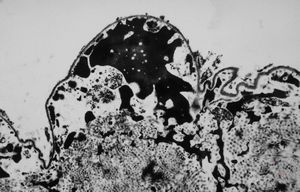

F,17y. | dystrophic calcification in a scar

M,63y. | dystrophic calcification in plexus chorioides

M, | dystrophic calcification and malaric pigment - brain